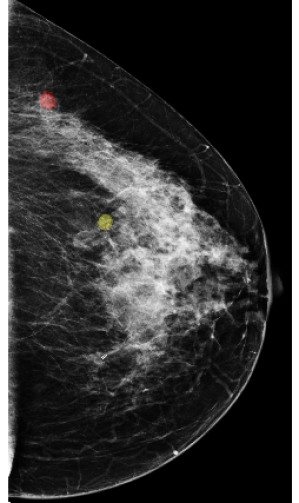

In this study, we consider lesion-level classification, and design models to directly distinguish biopsy-confirmed lesions as being either benign or malignant. With this strategy, we enable the models to make accurate lesion-wise predictions. To show that deep learning approaches can benefit from utilizing global image context in classifying local findings on mammograms, we first train DNNs with cropped image patches to enable the learning of fine details from a specific region, then integrate the extracted local information with the global context. The global context is provided in the form of saliency maps (Figure 2) extracted by a model classifying the entire image. Here we use Globally-Aware Multiple Instance Classifier [17] as the model to provide such saliency maps. In addition, we evaluate the models’ performance on a challenging population which consists only of cases that are difficult to diagnose and the radiologist requested a biopsy for. This further differentiates our work from previous works [16, 30, 17, 13, 18] and makes our results not directly comparable to theirs. This is because these methods were developed and evaluated for the screening population, which contains a lot of negative cases not requiring biopsy, which can inflate their evaluation metrics [16].

![]() |

The first type of maps are saliency maps which represent global context. We generate the saliency maps by training a network on full-resolution mammography images to predict the presence of benign and malignant lesions in the breast. We refer to this network as the “context network.” We use Globally-Aware Multiple Instance Classifier [30, 17] as the context network, which is explicitly designed to provide interpretability by highlighting the most informative regions of the input images. To be more precise, the feature maps obtained after the last residual block of the context network are transformed by a convolutional layer with sigmoid activation into two saliency maps, denoted as and . Each pixel in the saliency map corresponds to a region in the full image, and its element denotes a score indicating the contribution of this region towards classifying the input image as containing malignant lesions or benign tissues. A pair of saliency maps for an image is shown in Figure 2.